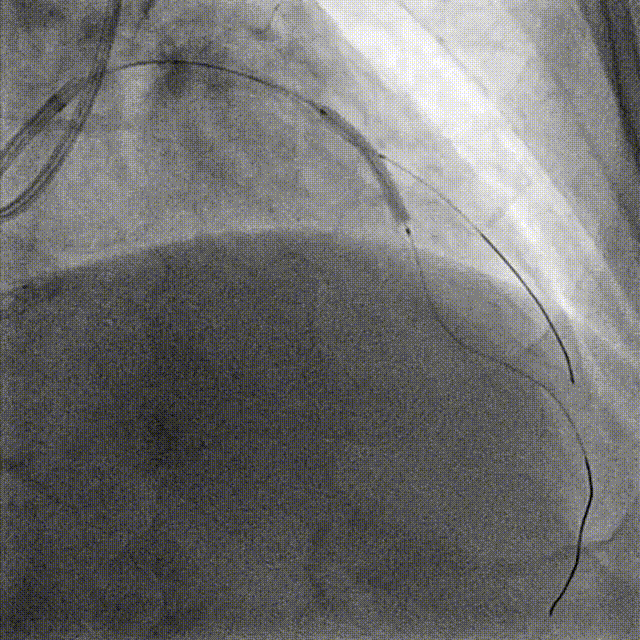

PCI-LAD TR, 7F EBU3.5

ROTA with 2.0mm burr

Angiography & Angioplasty NC 2.5*12mm

Stenting DES 2.5*24mm

Stent Optimization NC 2.5*12mm + NC 2.75*8mm

Lesion Preparation Cutting balloon 2.75*10mm @ 14atm

DCB Angioplasty DCB 2.75*25mm @ 8atm, 60s

Final Results